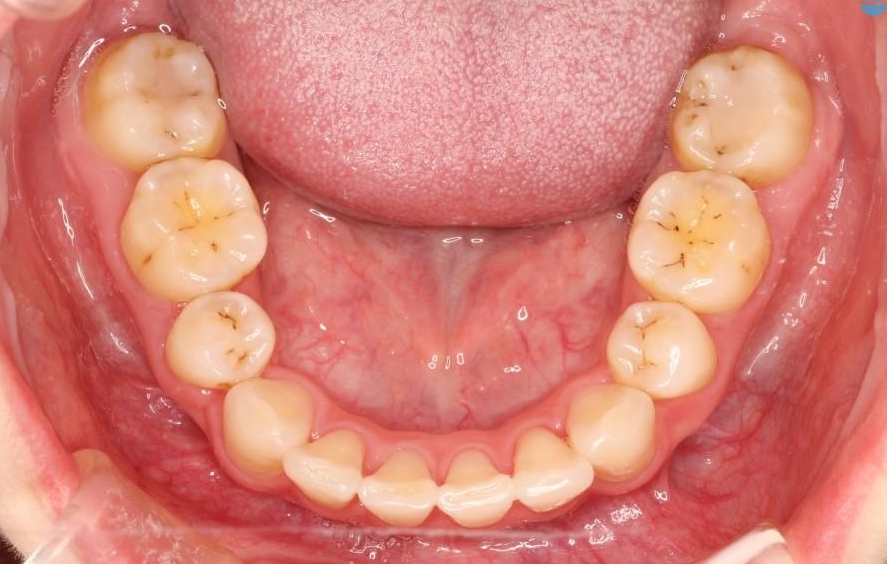

【20代女性】出っ歯の矯正 治療例

口元が出ていることを気にされて来院されました。

治療費の安い矯正治療を希望されていたため、メタルのワイヤー装置にて治療する計画にしました。また、歯みがきが苦手だったため、矯正治療をする前に徹底的にブラッシング指導を行いました。

出ている歯を引っ込めるためのスペースを作るため、上下左右の小臼歯を抜歯し、ワイヤー矯正を行いました。治療後は、口元がスッキリとしたことで患者様にも喜んでいいただきました。